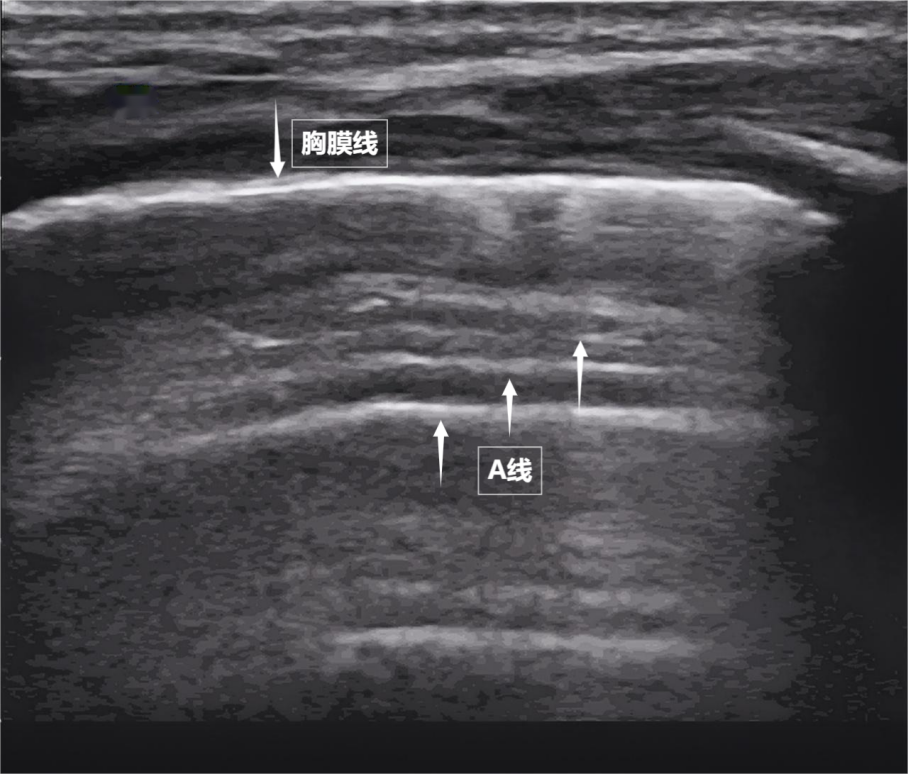

第一幕:《岸与浪》——胸膜线与线

当声波穿过胸壁的肋骨间隙时,首先遇到靠近肺部表面的光滑膜——壁层胸膜和脏层胸膜。两者紧密接触,中间没有多余的气体或液体。它们在屏幕上显示为明亮、平滑的水平线,共同形成胸膜线。这条线是肺部的“海岸”。在它的下方,由于肺泡内大量气体的声音的强烈反射,出现了一系列平行于胸膜线、等间隔、反复出现的明亮平行线,延伸像波浪一样深入屏幕。这是A线(见下图)

)。 A 线是肺正常通气的常见标志。它的存在直接表明肺表面含有足够的空气,胸膜腔内没有异常的液体或气体。

图为新生儿肺部正常超声表现